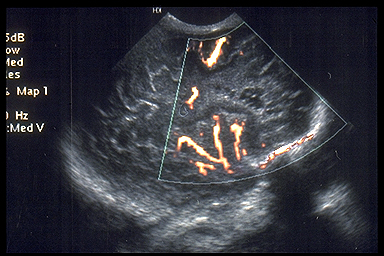

o

Color

Doppler can also show the loss of the semicircular loop of the pericallosal

artery (8)

Callosal Agenesis – absent cingulated gyrus and pericallosal artery |

Normal Corpus Callosum – normal pericallosal artery |